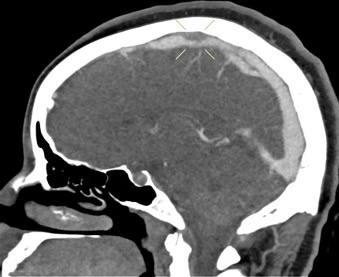

Diagnostic Testing. The patient’s CT brain imaging revealed a small amount of air in both frontal horns of the lateral ventricles (Figure 1). Her brain CTA revealed distension of the superior sagittal sinus (SSS), inferior sagittal sinus, transverse sinus, and vein of Galen and an extra-axial SSS defect (Figures 2-4). The initial report of the MRI brain with and without contrast redemonstrated trace pneumocephalus but was otherwise unremarkable. Later review after 10 days, revealed pachymeningeal enhancement, venous sinus distension, and a filling defect in the SSS suggestive of venous sinus thrombosis (Figures 5, 6). Her MRI of the cervical spine did not reveal another cause of neck pain, and her urine protein was negative.

Fig. 2. Short segment filling defect of the mid portion of the superior sagittal sinus.